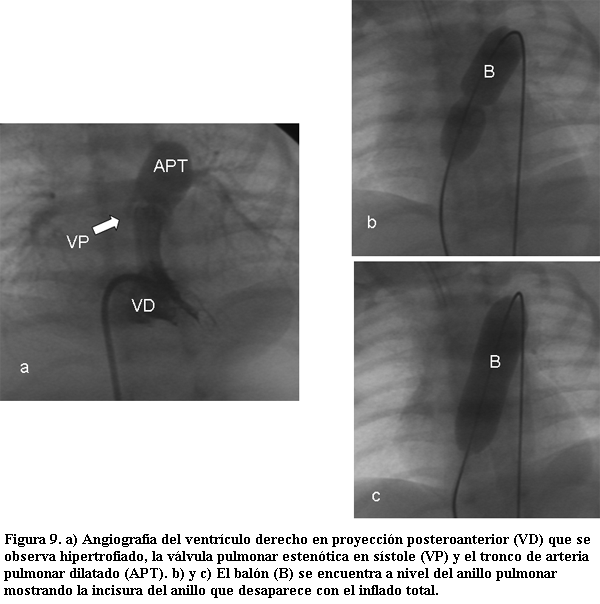

La dilatación de la válvula pulmonar por medio de catéter balón, descrita por Kan en 1982 (56), es el procedimiento terapéutico de elección para el tratamiento de la estenosis valvular pulmonar, aislada o asociada a otras entidades sin indicación de tratar o con indicación de tratamiento percutáneo. En general se acepta como indicación la presencia de un gradiente pico a pico entre la presión sistólica del ventrículo derecho y la presión sistólica de la arteria pulmonar, superior a 40 mmHg.

La elección del balón a utilizar depende de los datos aportados por el ETT y por la angiografía del ventrículo derecho realizada en proyecciones oblicua anterior derecha y lateral izquierda. De este modo sabremos: 1) si la válvula pulmonar es displásica (como puede verse en algunos síndromes genéticos: síndrome de Noonan); 2) el estado del infundíbulo pulmonar; y 3) fundamentalmente, el diámetro del anillo lo que nos permitirá elegir el tamaño del balón a emplear, el cual deberá ser de 1,2 a 1,5 veces superior; en caso de anillos mayores a 18 mm se deberán utilizar dos balones colocados a nivel del anillo pulmonar e inflados conjuntamente.

Los resultados dependen fundamentalmente de la variedad anatómica de estenosis pulmonar; así frente a la presencia de válvulas displásicas o con anillos menores al 45% del que le corresponde por superficie corporal, los resultados no serán óptimos, con índice de reestenosis elevado, por lo que pueden requerir nueva dilatación con balón o ir directamente a una corrección quirúrgica. Consideradas todas las estenosis valvulares pulmonares en general el índice global de reestenosis es bajo (menor al 5%). La reacción infundibular es directamente dependiente del grado de severidad de la estenosis pulmonar preexistente y posterior a la dilatación puede incluso incrementarse, pero con tendencia a la regresión espontánea en el término de 3 a 6 meses; si luego de la valvuloplastia persiste un gradiente residual a nivel infundibular pulmonar mayor a 50 mmHg el mismo se beneficia del uso de â bloqueantes, que se mantendrá por 6 meses.

Las complicaciones posibles en estos casos suelen ser menores, como sangrados y hematomas locales, arritmias; o mayores como la perforación o rotura de la pared ventricular o de la arteria pulmonar, situación muy infrecuente. A largo plazo se describe la incidencia de insuficiencia pulmonar entre el 30%-70% de los casos, dependiendo directamente del tamaño del balón utilizado (a mayor balón, con relación al anillo, mayor posibilidad de daño) y de las características de la válvula pulmonar (cuanto mas displásica, con valvas más rígidas sin clara separación de los rafes entre las valvas, mayor posibilidad de quedar insuficiente) (tabla 6, figura 9) (57-59).